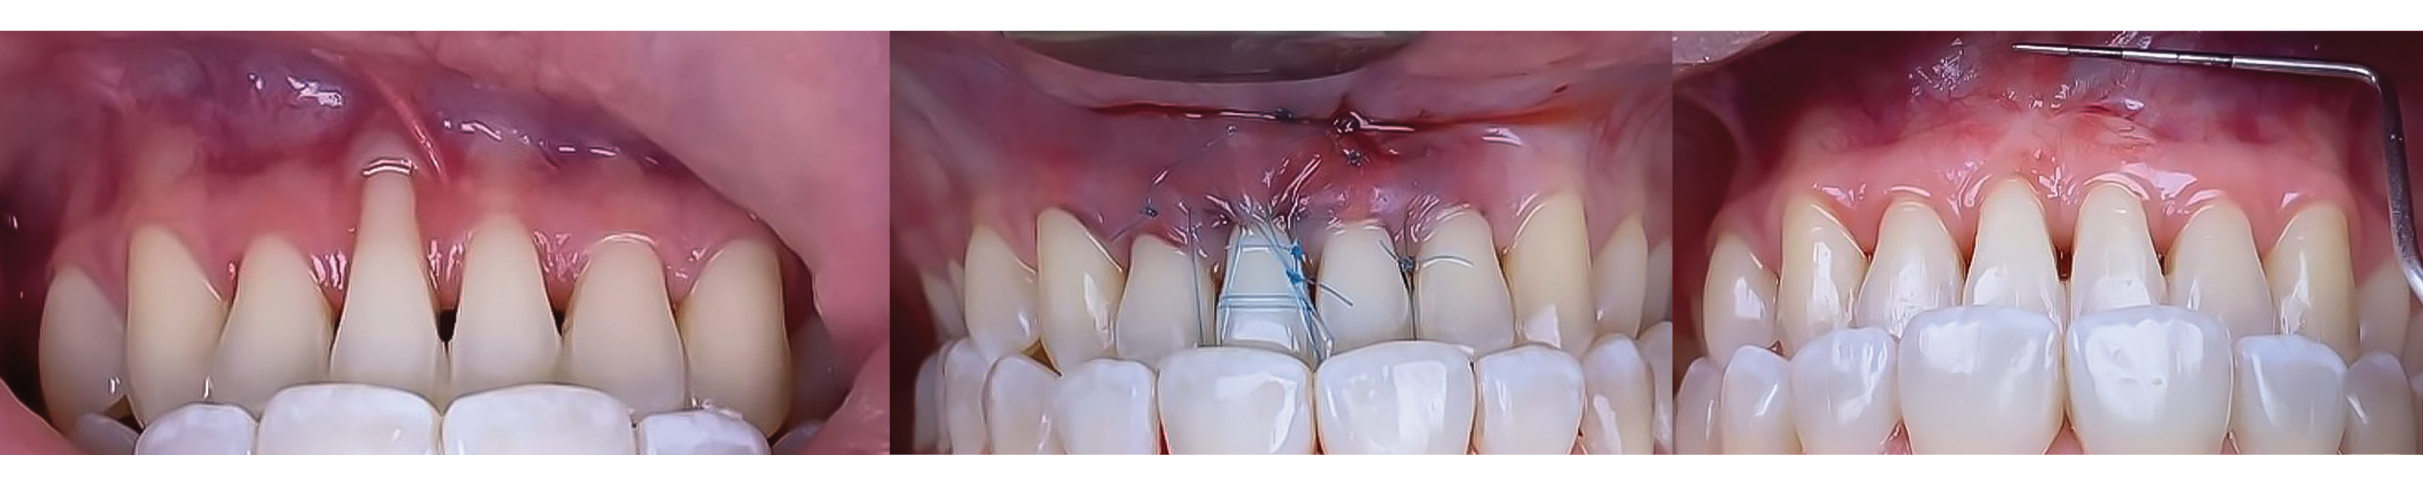

Soft tissue management and Tunnel Techniques. This two-day intensive course will provide participants with both theoretical foundations and practical experience in periodontal plastic surgery.

Through lectures, clinical case discussions, and hands-on practice, participants will learn advanced surgical techniques for root coverage, soft tissue grafting, and esthetic enhancement in periodontal procedures.

Soft tissue management and Tunnel Techniques. This two-day intensive course will provide participants with both theoretical foundations and practical experience in periodontal plastic surgery.

Through lectures, clinical case discussions, and hands-on practice, participants will learn advanced surgical techniques for root coverage, soft tissue grafting, and esthetic enhancement in periodontal procedures.

Coronally Advanced Flap for Isolated Recessions -Subepithelial Connective Tissue Graft |

Hands-OnCoronal Advanced Flap for Isolated Recessions and Multiple Recession |

Modified Coronally Advanced Tunnel Technique with Vertical Incisions (VISTA). |

Hands-OnModified Coronally Advanced Tunnel Technique |